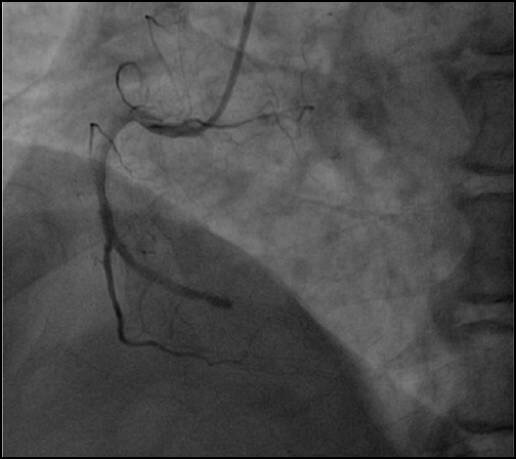

本文为经导管主动脉瓣置入术相关未决问题第二部分,着重介绍了TAVI的手术方式及手术预后情况,以下为Part2的相关要点。一、手术途径问题为患者选择适宜的手术…